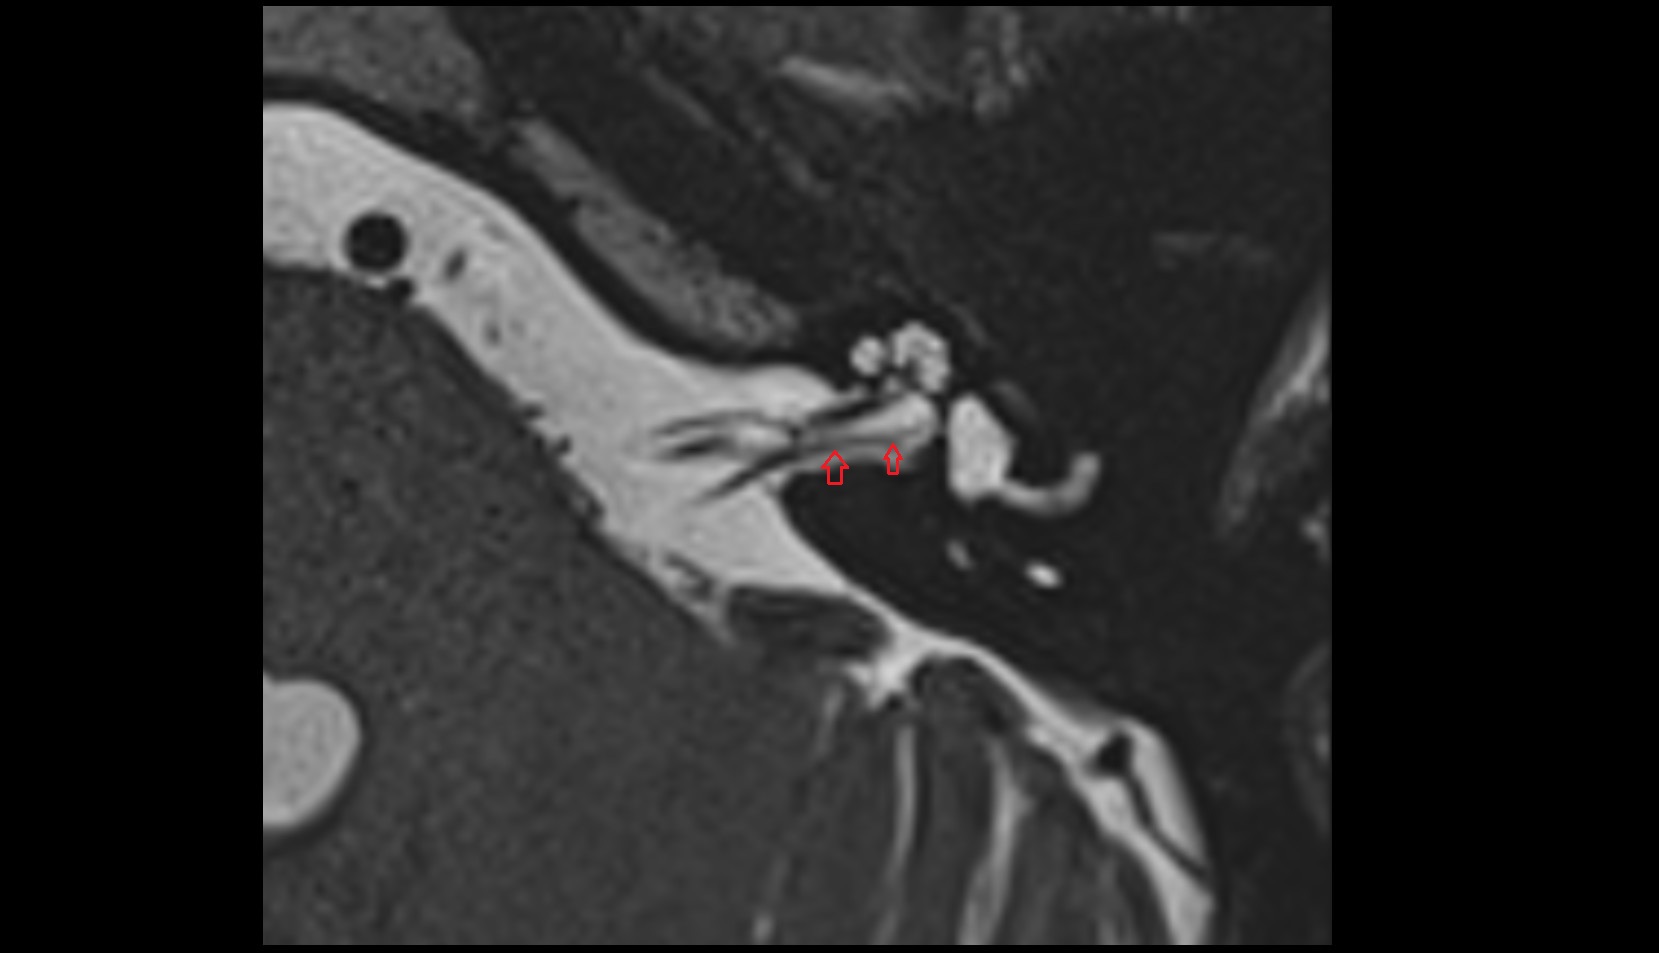

- Temporomandibular joint

- Articular disc of temporomandibular joint

- Articular eminence

- Mandibular condyle

- Mandibular fossa

- Superior head of lateral pterygoid muscle

- Inferior head of lateral pterygoid muscle